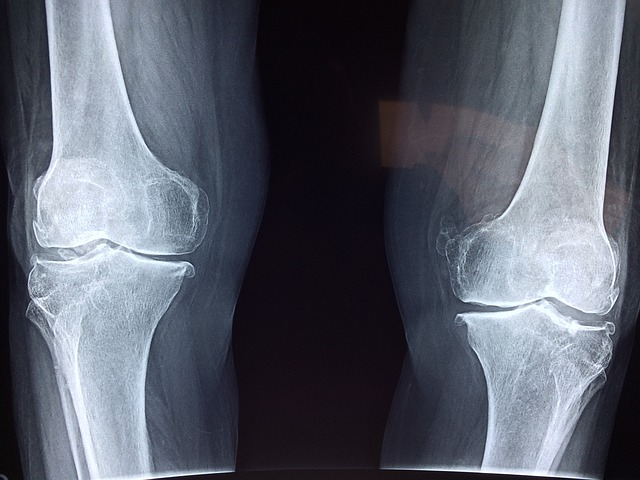

Finding Relief Naturally: Simple Home Remedies for Knee Pain

Living with knee pain can be challenging, but there are simple Natural Home Remedies for Knee Pain you can try at home without needing to rush to the doctor. These natural solutions may help alleviate discomfort and improve your quality of life.